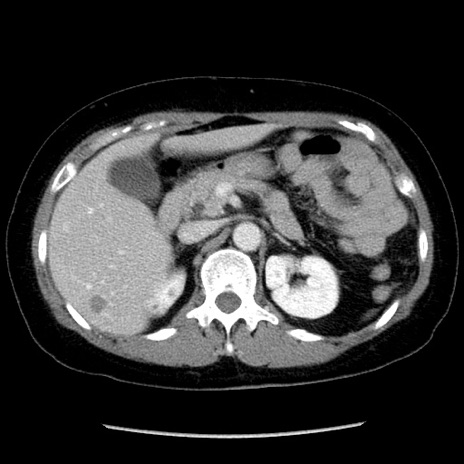

冠状断像